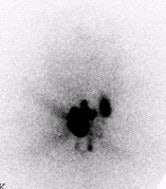

![]() |

Above, an 131I diagnostic scan. Below, a post-therapeutic 131I scan. In these three patients who received 131I therapy the same day as the diagnostic scan, stunned thyroid lesions failed to take up any of the therapeutic dose. Images courtesy of Dr. Hee Myung Park.